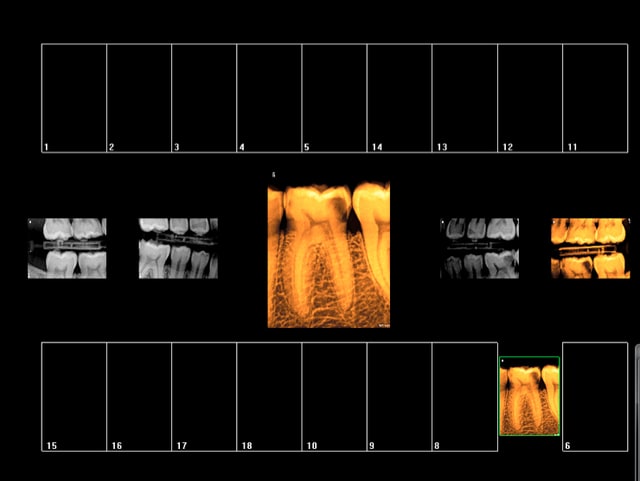

Rebelote aujourd'hui. Pulpite sur 15.

Re re belote. pulpite 38. -))))

Pas venu depuis 2007 date de la pose d'onlays sur 45 46.

On va pas refaire le débat, mais ou bien je suis un mutilator, ou bien je suis lobotomisé, mais il ne me semble pas aberrant de poser IC/Cr sur cette 15 non ?, je me vois pas y coller un onlay.

Après Chicot, on a les mêmes qui consultent quand ça picote sérieux, et en général l'indication du coiffage MTA,biodentine/inlay/onlay, n'est plus vraiment d'actualité.

En général c'est déjà limite pour la couronne alors ...

Suivant : 47 pétée en distal mais pas de douleur ( dernier RDV 2008) . Chiotte elle pouvait pas attendre un peu avant de péter ? j'aime bien les actes qui solvabilisent à la fois le patient et le praticien pas ces soins opposables à un tarif de merde. -)))

Ah ! enfin une endo au résultat non aléatoire sur 36 ! spéciale dédicace pour améli ! -))))

Suivant : 45 cassée ( jadis un onlay support de bridge ? ) Dent gardée vivante puis endo à travers l'onlay je suppose. ca marche moins bien après forcément. -))))

Maintenant la question que je me pose , vais je continuer à soigner les caries moyennes révélées ailleurs par les radios ? Vu qu'on nous prend pour des cons, hein ?

En plus faire les radios et les coter c'est prendre le risque de se faire emmerder par un CDC, autant ne plus en faire non ? ca résoud le problème de conscience que je pourrais me poser à l'avenir ! Il suffira d'attendre les signes d'appels et d'avoir des stocks de R25 ! -))))

Suivant : douleurs 36. Abcès du à un Syndrome du septum dent vivante, dommage.......-)))))

Dernier rendez vous chez le dentiste : 12 ans ( extractions des sagesses)

Notez l'indication des rétro coronaires et de la rétro alvéolaire dans ce cas : pas d'antécédents de soins intensifs et atteinte pulpaire suspectée ( élimination d'un 4ième degré, fais le test au froid après) . -)))))